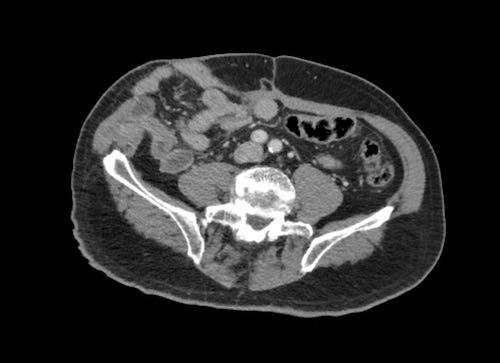

Hình ảnh

Hình ảnh CT của một bệnh nhân ung thư phúc mạc.

Một lượng nhỏ dịch cổ trướng hiện diện ở góc phần tư trước bên phải.

Các đường dày dạng nốt vuông góc với thành ruột được ghi nhận.

Hình ảnh này đại diện cho tổn thương xâm lấn mạc treo ruột lan rộng (mũi tên).